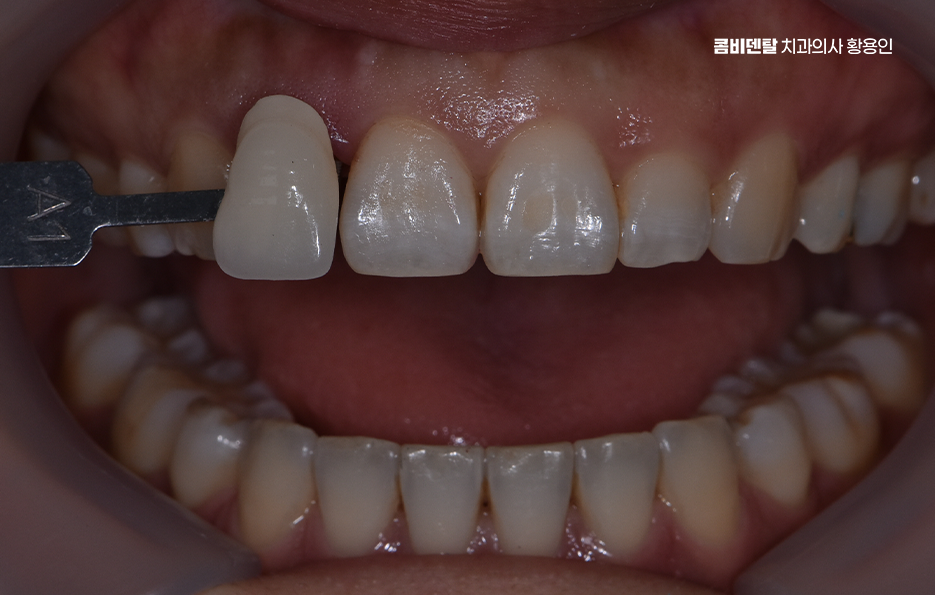

앞니 올세라믹 마지막 단계는 완성된 올세라믹 크라운을 치아에 접착하고, 교합을 조정하는 마무리 단계로 이때 중요한 건 주변 치아와 얼마나 조화롭게 어우러지는지를 보는 거예요. 색상은 단순히 ‘흰색’ 하나로 결정되는 게 아니라, 투명도, 밝기, 색조까지 섬세하게 조정돼야 하고 특히 앞니는 음식을 자르거나 말할 때 중요한 기능을 하기 때문에, 교합, 즉 맞물림이 정확해야 장기간 사용할 수 있어요.

올세라믹이라는 건 말 그대로 금속이 전혀 들어가지 않은 순수 도자기 재질로 만들어진 보철물을 말하는데 금속이 없기 때문에 빛이 투과되는 방식이나 색상의 자연스러움이 실제 치아와 거의 흡사해서, 앞니처럼 시선이 집중되는 부위에 사용하면 주변 치아와의 경계가 거의 티 나지 않게 복원이 가능하며 특히 사진 찍을 때나 밝은 빛 아래에서도 회색 그림자나 반사광이 없기 때문에 심미적인 치료가 가능하다고 볼 수 있어요